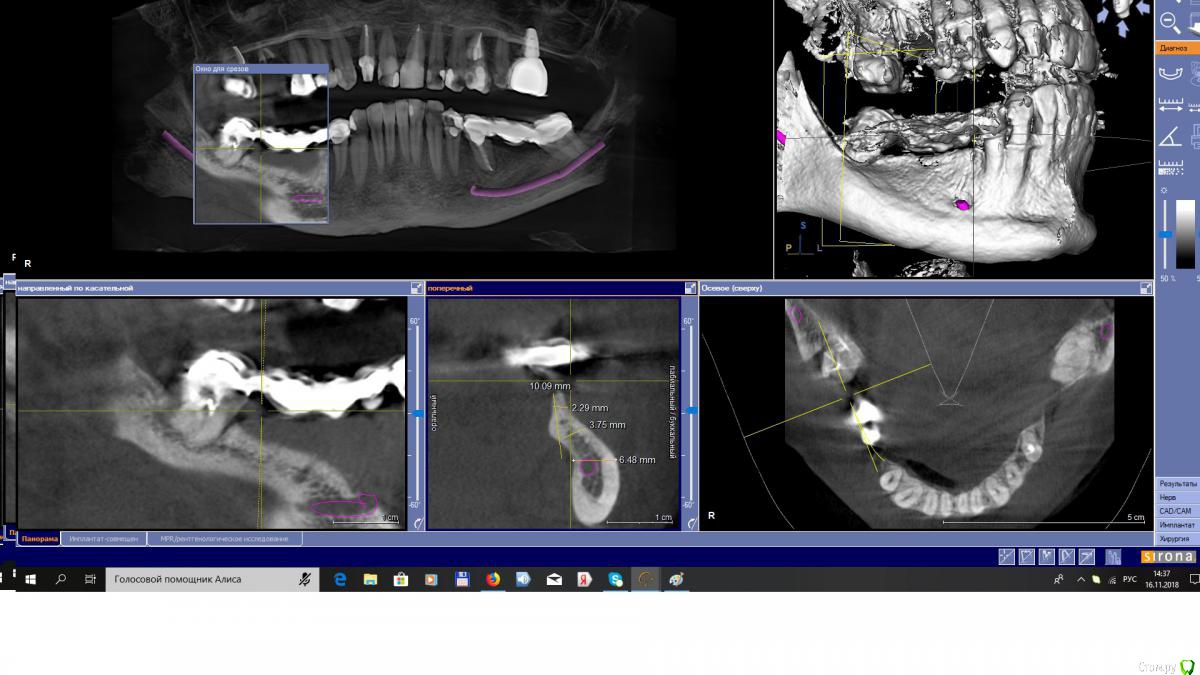

EEcho Опубликовано 16 ноября, 2018 Поделиться Опубликовано 16 ноября, 2018 Коллеги, добрый день!Ваши варианты при такой атрофии. Ссылка на комментарий

EEcho Опубликовано 22 ноября, 2018 Автор Поделиться Опубликовано 22 ноября, 2018 Это понятно, что можно любую методику кроме расщепления и моноблоков, но как в этом случае обойти ментальное отверстие с выходом сосудисто-нервного пучка почти вертикально? Резать мембрану обходя отверстие и бить кнопки вокруг, то есть сосиську по Урбану, с эволюшкой.? или делать каркас из мини пластин.? полужестким каркасом отверстие будет не обойти.( возможно графт будет через него высыпаться или врастет через него соединительная ткань)? Ссылка на комментарий

АнтонТЛТ Опубликовано 22 ноября, 2018 Поделиться Опубликовано 22 ноября, 2018 Если ментальное отверстие напрягает, нарастить до него и поставьте имплантат покороче 1 Ссылка на комментарий